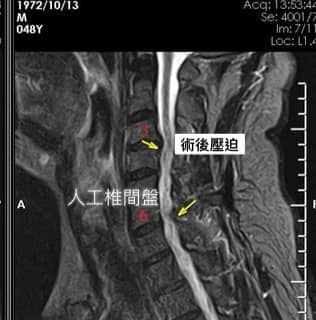

Cervical Spine Treatment Cases 頸椎治療案例 頸椎過直會導致肩膀酸痛嗎?中醫微創針刀療法成功改善頸椎弧度 2021.11.03 頸椎骨刺導致步態不穩、半身麻痛,一定要開刀嗎?中醫針刀治療100天改善實例公開 2021.10.07 冷水刺痛全身、下肢異常竟源自頸椎壓迫?MRI對比揭示非手術療法改善實證 2021.10.08 伏地挺身突然做不到?竟是C6C7頸椎壓迫導致神經肌力減退!中醫微創療法10週改善 2021.09.11 低頭族小心!頸椎滑脫竟導致長期頭痛肩痛與睡眠障礙|12次中醫微創治療成功矯正滑脫 2021.07.16 醫案實證:術後再發的脊髓壓迫症也能靠中醫療法改善 2021.07.10 手術後腳還是麻?頸椎開刀半年症狀未解,靠中醫微創8次改善右腳無力與手麻! 2021.06.30 狂送急診四次竟查不出病因!胸悶心悸原來是頸椎壓迫,靠針刀微創13次改善 2021.06.09 後縱韌帶鈣化壓迫脊髓!步態不穩、手腳麻木竟可逆轉?14週22次針刀治療真實見證 2021.05.06 什麼是中樞型脊髓型頸椎病?症狀、診斷與治療全解析 2021.05.28 神經根型頸椎病症狀解析:肩麻、手痛與肌肉萎縮 2021.04.16 嚴重心悸胸悶竟是頸椎問題!交感神經型頸椎病針治2次症狀明顯改善|真實病例與患者疼... 2021.04.07 從心悸胸悶到手麻夜痛難眠,她竟是頸椎壓迫!真實MRI對比見證中醫逆轉勝療效 2021.04.04 從手腳無力到步態不穩,他竟是頸椎脊髓型壓迫!三個月密集針刀療法逆轉勝|台北蔡大哥... 2021.03.31 頸椎椎間盤突出要一次動四節嗎?手術vs.保守治療完整解析 2021.03.27 ← 上一頁 2 3 4 5 6 下一頁 →